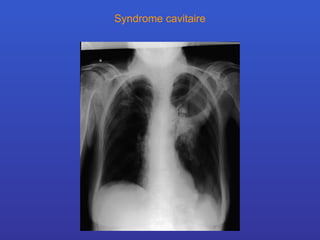

Syndromes radiologiques Syndrome cavitaire

Définition: Le syndrome cavitaire est défini par la présence d’une ou plusieurs cavités néoformées dans le parenchyme pulmonaire. Critère  radiologiques L’aspect radiologique varie en fonction : taille des cavités épaisseur de leur paroi contenu (  air, solide, niveau hydro-aérique  )

Syndrome cavitaire